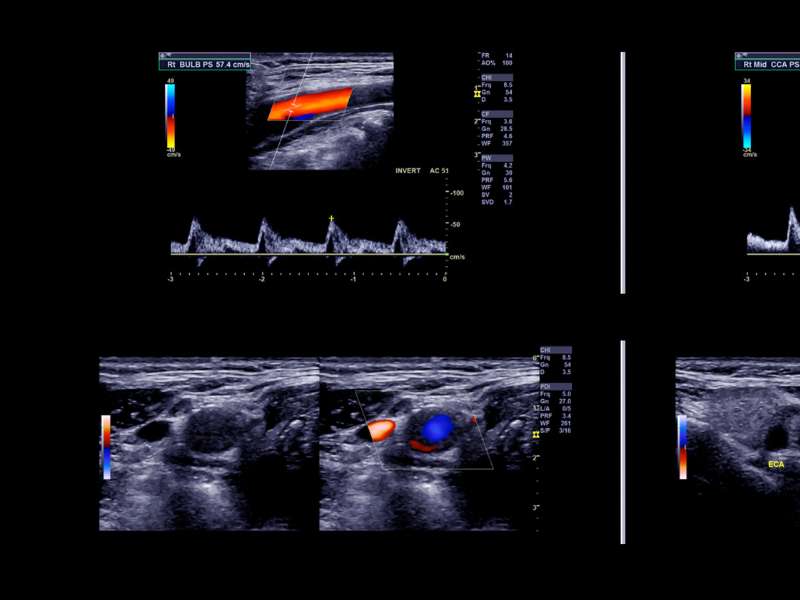

Antes de detalhar as etapas de preparação, é vital entender a função do Doppler venoso. Este procedimento utiliza ondas sonoras de alta frequência para criar imagens das estruturas internas do corpo e, principalmente, medir a velocidade e a direção do fluxo de sangue. A preparação tem como principal meta eliminar qualquer interferência que possa obscurecer essas ondas sonoras ou dificultar o acesso do transdutor à pele. Por exemplo, resíduos de cremes, óleos ou talcos na pele podem criar uma barreira ou artefatos que comprometem a visualização do fluxo e das paredes das veias. Quando o paciente não se prepara corretamente, há um risco real de o especialista não conseguir detectar alterações sutis no sangue, resultando em um diagnóstico inconclusivo ou até mesmo incorreto. Portanto, as orientações de preparo são desenhadas para maximizar a área de contato e a qualidade da imagem, permitindo que o médico avalie o estado vascular com a precisão exigida.